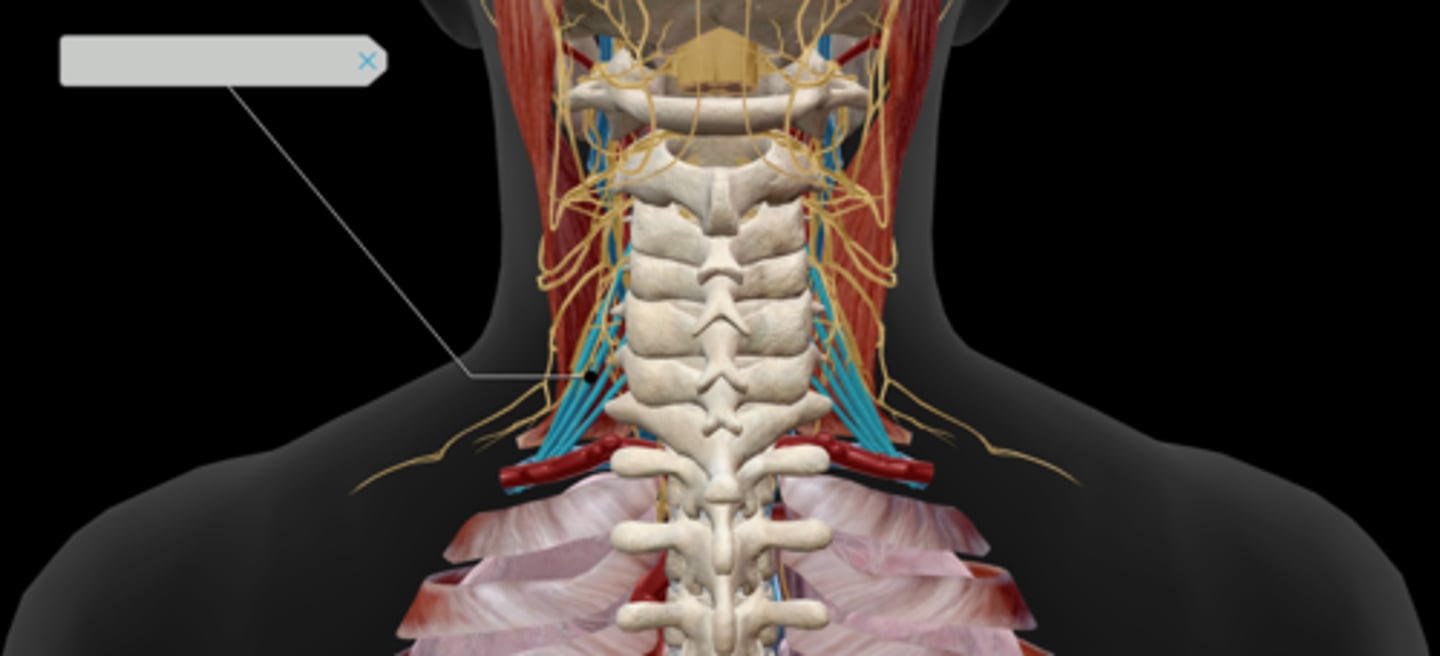

Scalenes